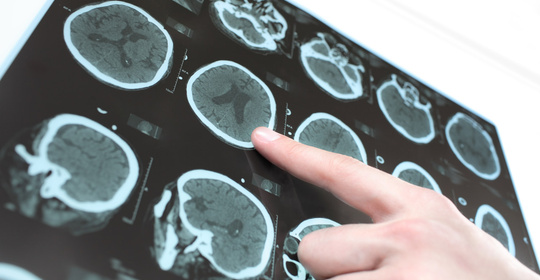

短暫性腦缺血發作的診斷與治療方法

創傷性腦損傷的診斷、治療與預防

毛毛樣腦血管病的診斷、治療及預防